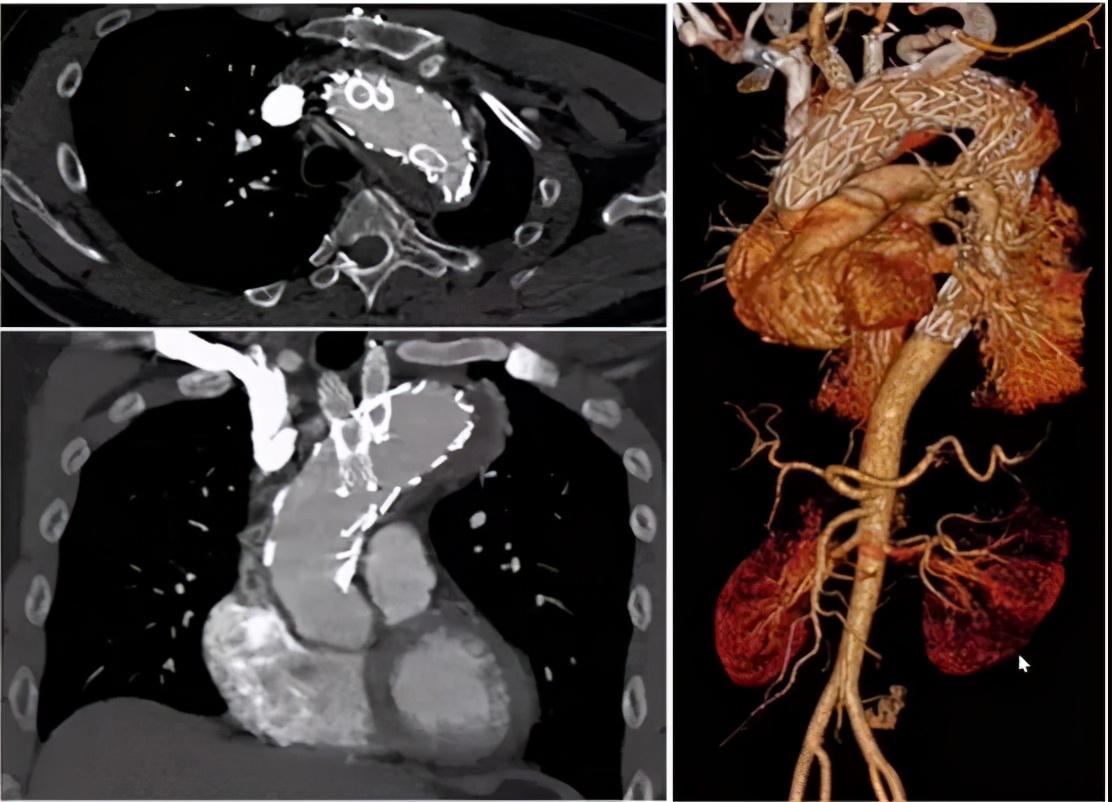

病例2(男性,66岁)

主诉:急性胸背痛1天余。

既往史:高血压。

手术史:5年前因Debakey Ⅱ型夹层行升主动脉置换术。

查体及实验室检查:血肌酐196 umol/L。

手术关注点:弓部动脉瘤原位开窗操作难度大,术中存在较大风险;而如果使用烟囱支架,则内漏风险大。所以,决定行预开窗+体外缝制内分支,增加重建弓上分支成功率,降低术中缺血风险、内漏风险。

手术方法:弓上三分支预开窗+内分支+主动脉腔内修复术。

手术步骤:弓上分支体外预开窗+内分支缝合;释放远端限制支架+近端主体支架;弓上分支支架植入。